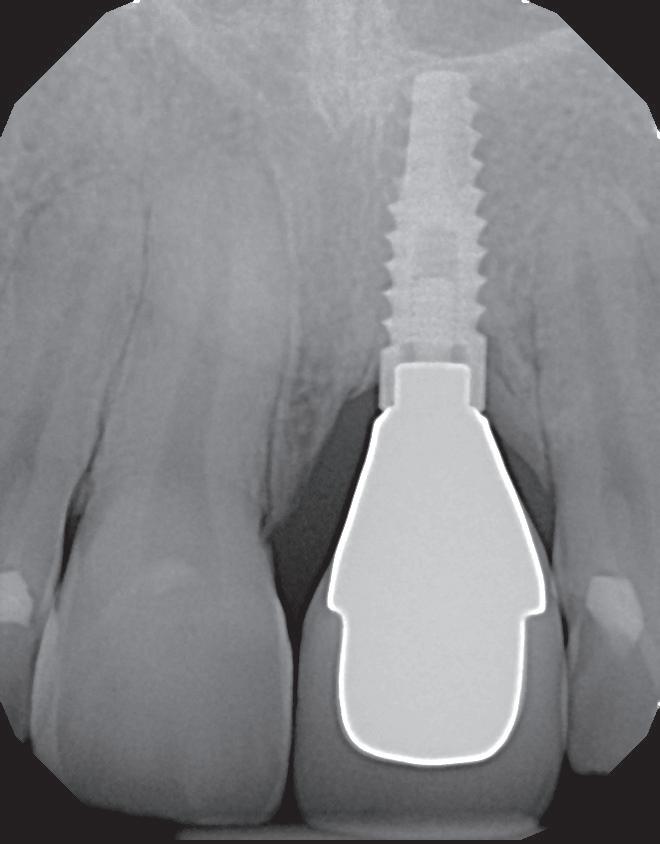

De asemenea, trebuie evaluate anual modificările radiografice. În ședința de inserție a restaurării, se înregistrează o radiografie bitewing standardizată pentru a permite evaluarea anuală a modificărilor osoase din jurul implantului. Remodelarea osului alveolar în primul an este bine documentată și depinde de tipul de implant utilizat; cu toate acestea, nu ar trebui să apară apical de primul filet al implantului. Prin urmare, este importantă abilitatea de a vizualiza filetele implantului pe radiografii. Modificările pierderii osoase de 2 mm sau mai mult după primul an reprezintă un semn de periimplantită. De îndată ce pierderea osoasă este recunoscută, pacientului trebuie să i se recomande terapia imediată pentru a opri procesul de boală.

și „punte cu trei unități”, în prezent fiind la egalitate cu majoritatea sistemelor de titan. Deși datele pe termen lung nu au confirmat încă aceste rezultate bune, succesul de până acum este încurajator, astfel încât clinicienii profită de beneficiile clinice ale dioxidului de zirconiu în practica zilnică, introducând implanturile ceramice ca opțiune suplimentară în spectrul de opțiuni alături de cele de titan (fig. 1). Chiar

În plus, aceste proprietăți bioinerte par să aibă și beneficii în ceea ce privește dezvoltarea periimplantitei și calitatea țesuturilor moi. În comparație cu titanul, dioxidul de zirconiu prezintă acumulare de placă și aderență bacteriană mai redusă, precum și o grosime mai mică a biofilmului depus. Și fluxul sanguin circulant către țesuturile moi este mai asemănător cu cel al unui dinte natural în cazul ceramicii față de titan, care oferă flux sanguin redus semnificativ. Se știe că o circulație sanguină mai bună înseamnă țesuturi moi mai sănătoase, care, la rândul lor, prezintă rezultate estetice îmbunătățite. Deși deocamdată lipsesc dovezile pe termen lung pentru implanturile ceramice, sunt disponibile rezultatele inițiale la 3 și 5 ani, iar tendința, susținută de studii preclinice și experiența clinică, este că dioxidul de zirconiu demonstrează același rezultat - iar în unele studii chiar o pierdere osoasă marginală mai redusă față de implanturile de titan. În această perioadă încă nu s-a descris clinic periimplantită.

1. Implanturi din titan (stânga) și zirconiu (dreapta). 2. Recesii la implanturile ceramice (stânga) și din titan (dreapta). 3. Țesut moale cu implant din zirconia, lipsit de inflamație.

4. Structura cristalină a ceramicii TZP.